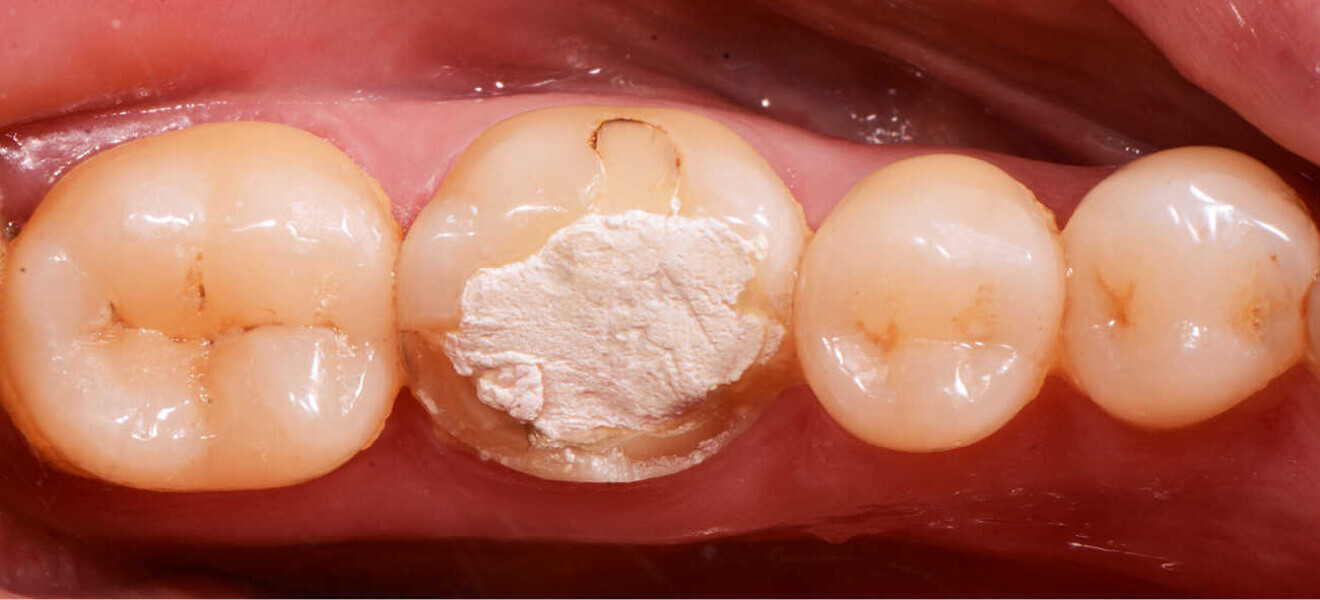

Fig. 2. Situación después de la reconstrucción del muñón con resina (Tetric N-Ceram Bulk Fill) y la preparación del muñón.